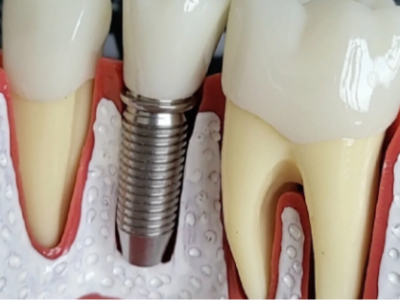

我們知道種植義齒也叫人工種植牙,它是將與人體骨質(zhì)兼容性高的生物材料(一般稱作種植體)植入牙槽骨中,然后在種植體上做出假牙的一種修復(fù)方式,通過手術(shù)的方式我們把種植體放進牙槽骨中,那么這一部分就相當于天然…